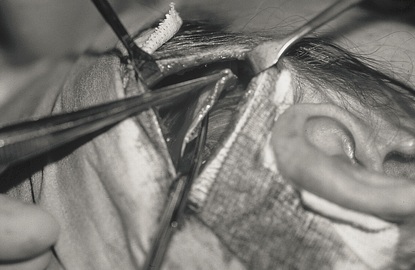

Temporalis Fascia 摘取